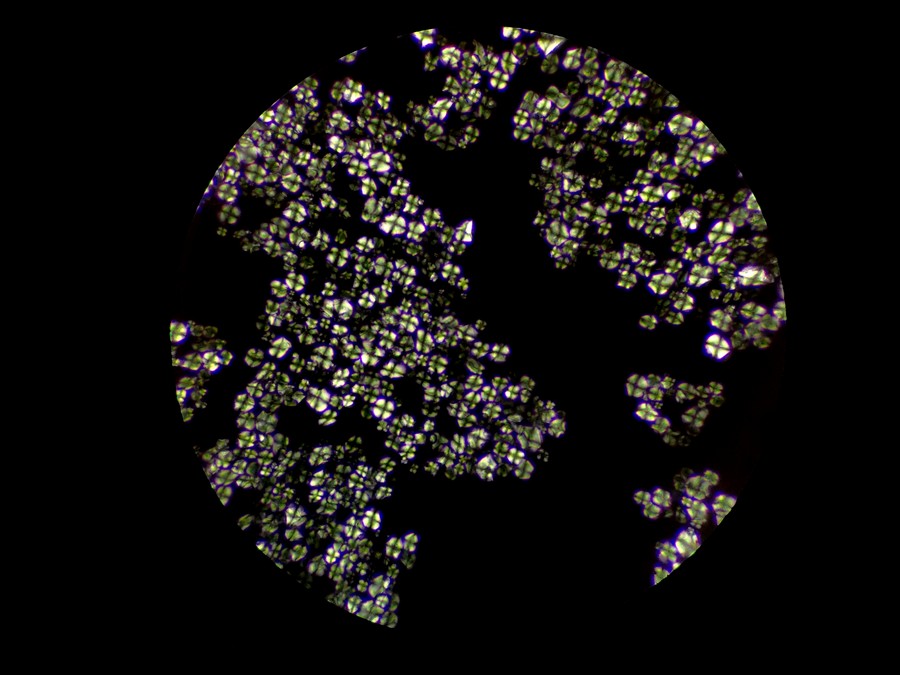

偏光观察的下中药粉末

中药粉末可用生物显微镜和偏光显微镜进行观察,中药粉末包含的草药栓细胞、导管等结构可用明场型态观察鉴定,而草酸钙簇晶和淀粉等成分则可以用偏光观察鉴定。

但为什么我们在中药颗粒里只看到淀粉,没有发现中药成分呢?这是因为中药颗粒生产工艺非常精密。中药粉剂是把中药粉碎加工制成干燥粉末,而中药颗粒不是中药粉剂做出来的,其生产流程是通过把药材和乙醇或水加入到提取罐中,进行长时间煎煮提取出有效成分,再浓缩处理成浓缩液,加入到淀粉等辅料中,再制粒分装成一包包的中药颗粒,也就是说,中药颗粒只保留了从药材提取出来的有效成分,不保留药材本身,所以是看不到中药成分的。

中药颗粒在镜下可见的成分是淀粉辅料,可在偏光观察下形成偏光十字,而其有效成分是提取浓缩出来的中药分子,无法用显微镜观察,需要通过液相色谱等方法才能检测。